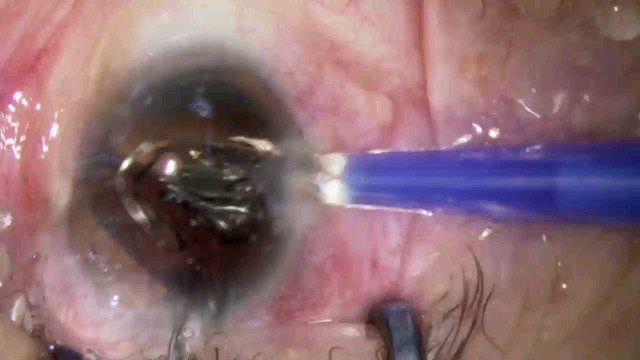

大瓜:湖南省人民医院副院长出轨眼科主任?

号外号外,湖南省人民医院副院长祖雄兵和眼科主任医师曾琦被指存在不正当关系,并有不雅视频传出。对此,医院工作人员回应:组织正在调查,请给医院宣传部门联系。当地卫生健康委员会对此回应:暂未接到相关的信访反映。祖雄兵为湖南省人民医院副院长,泌尿外科学科带头人。曾琦,博士,主任医师,硕士研究生导师。现任湖南省人民医院眼科副主任、眼科一病区主任,湖南省卫生健康高层次青年骨干人才,湖南省预防医学会眼病防治专业委员会主任委员、湖南省女医师协会眼科专业委员会主任委员、湖南省医学会眼科学专业委员会防盲学组副组长、湖南省医学会眼科学专业委员会眼外伤及职业病学组副组长、湖南省医学会眼科学专业委员会白内障学组副组长、